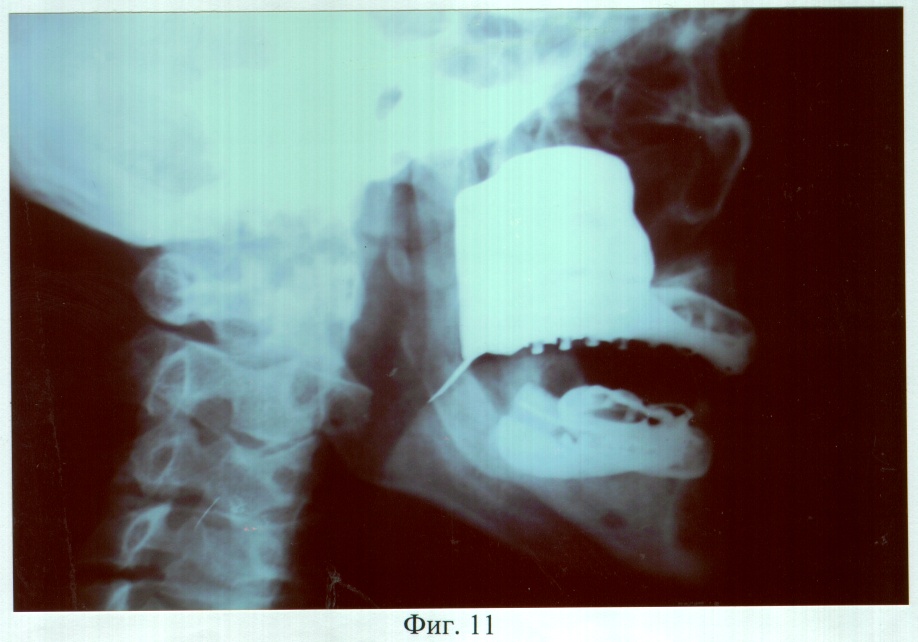

На фиг.11 – рентгенограмма больного М. через 3 года после ортопедического лечения (левая латеральная проекция).

Адаптация к протезам наступила в течение семи дней, после чего больной отмечал удовлетворительное функциональное состояние зубочелюстного аппарата. Фонетическое обследование с помощью разработанного способа диагностики нарушений речевой функции (заявка на изобретение №2005104063, Россия: МКИ А61В 5/00, 5/12, А.А.Радкевич, В.Г.Галонский, приоритет от 15.02.2005 г.), включающее оценку произношения звуков и разборчивости речи (гнусавости) с помощью карты-опросника, с последующим математическим вычислением процента нарушения, показало, что до ортопедического лечения нарушено произношение звуков – б, в, д, з, и, к, л, м, р, т, х, ш, щ; k (коэффициент разборчивости речи) = 5; U (величина нарушения речевой функции) = 41,2%. После протезирования нарушено произношение звуков – д, л, т, ш, щ; k=3; U=8,7%. При осмотре через 2 года больной жалоб не предъявлял, состояние протезов удовлетворительное. Морфологические исследования слизистой оболочки протезного ложа и рентгенография костей лицевого скелета, проведенные до и через 6, 12, 24 и 36 месяцев после протезирования, показали отсутствие признаков воспаления и прогрессирования атрофии.